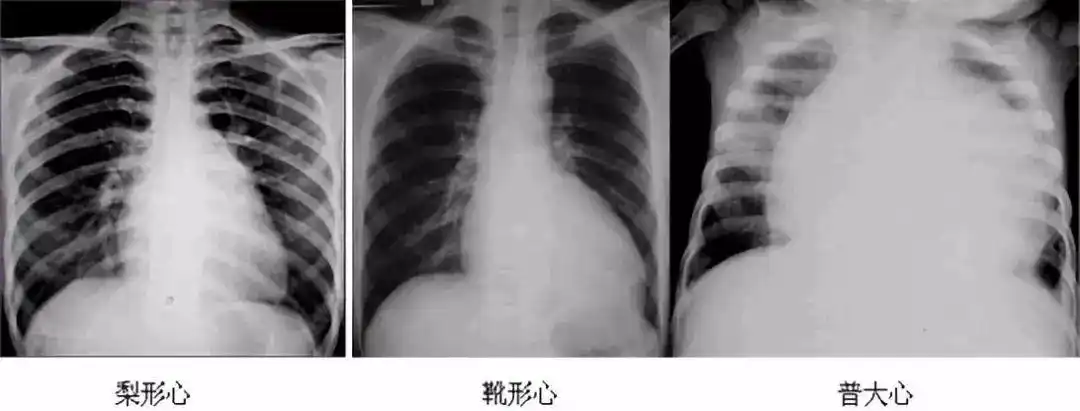

梨形心靴形心烧瓶心这也样看平片想不会都难